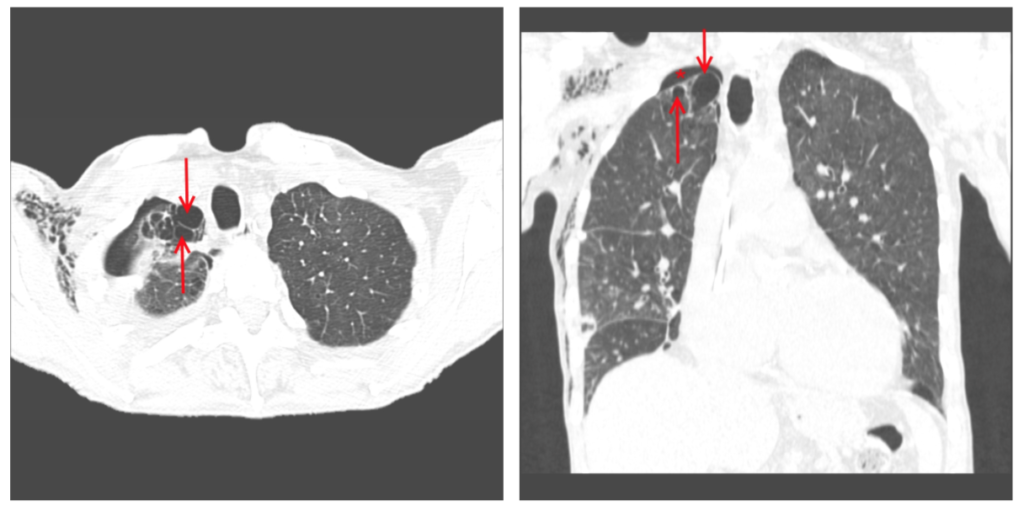

Буллёзная болезнь и пневмоторакс

Буллезная эмфизема легких